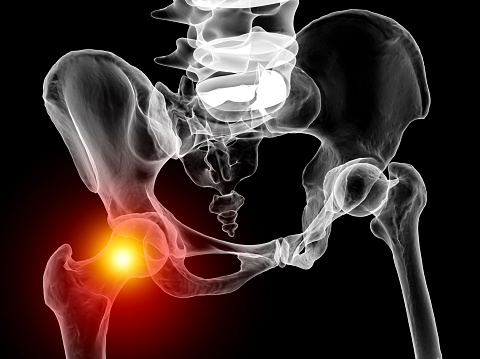

고관절의 특징

고관절은 골반과 대퇴골을 연결하는 골절입니다.

인체에서 가장 많은 체중을 지지하며 튼튼하고 안정적인 관절입니다.

어깨 관절 다음으로 두 번째로 운동범위가 큰 관절이며 ball-socket 형의 활막관절입니다.